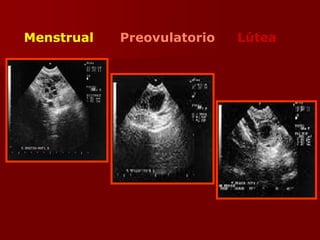

Menstrual Preovulatorio Lútea

Producción Ovárica de

Esteroides Sexuales